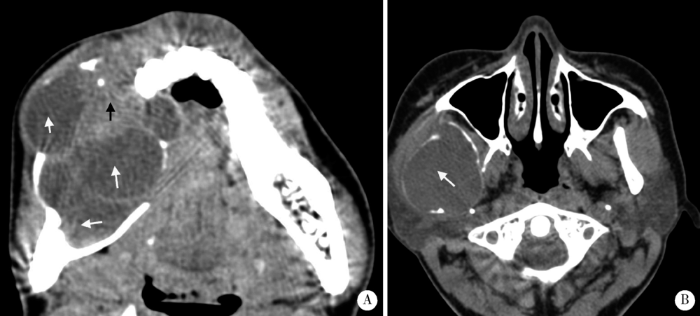

促结缔组织增生型成釉细胞瘤的边界形态特征

Figure 1

The boundary features of DA

A-B, DA shows scalloped shape with short sclerosed border on axial CT images (white arrows); C, Ill-defined border, infiltration into surrounding bone (white arrow) and locally destroyed cortex can be observed in DA; D, DA shows as solid mass on CT (black arrow).